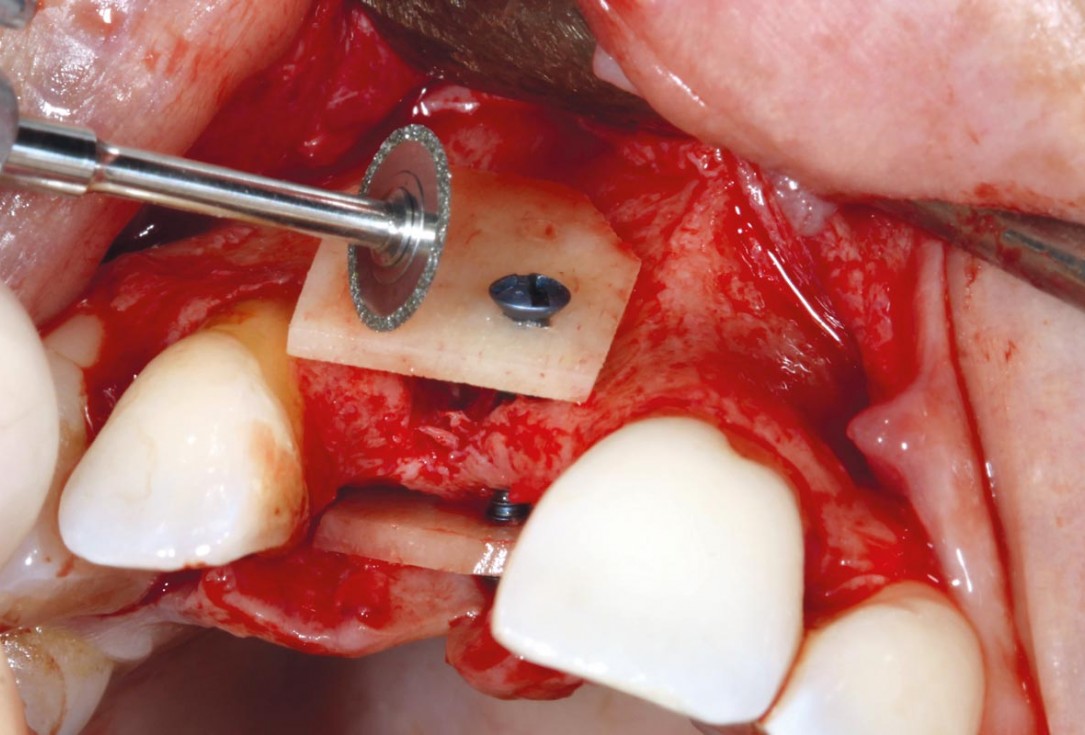

3/11 - Fixation of cortico facially and palatallymaxgraft® cortico at combined defect palatally and facially - Dr. K. Höckl

4/11 - Removal of sharp edgesmaxgraft® cortico at combined defect palatally and facially - Dr. K. Höckl